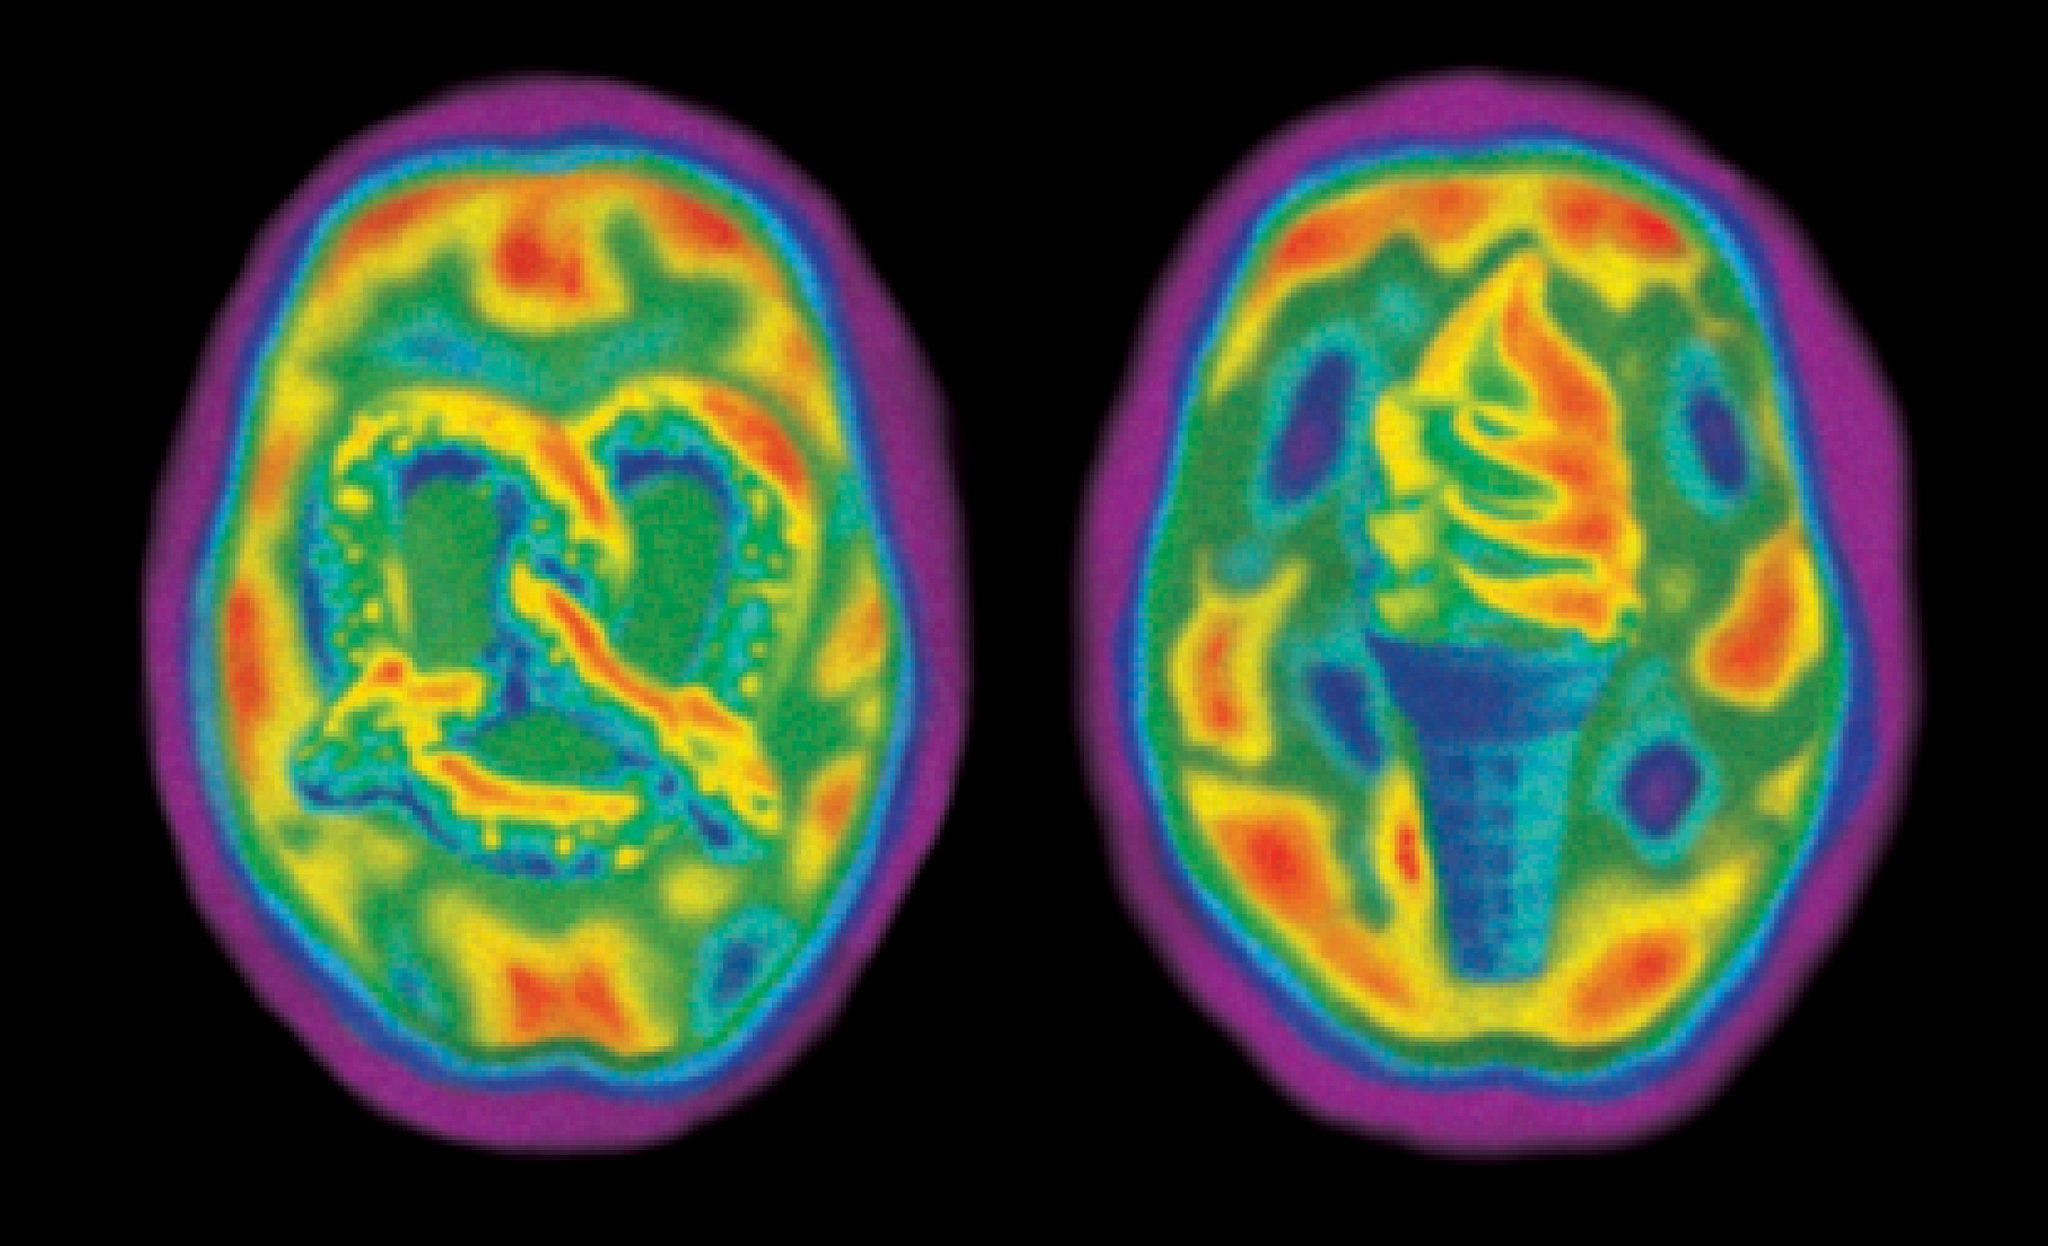

Ever found yourself stuck on a brain activity scan crossword clue? It can be frustrating to be so close to finishing a puzzle only to get stuck on that one elusive clue. But fear not, we’re here to help!

Whether it’s a PET scan or an fMRI, brain activity scans are fascinating tools used in the field of neuroscience. But when it comes to crossword puzzles, they can be a bit tricky to decipher. Let’s dive into some tips to crack that brain activity scan crossword clue!

brain activity scan crossword clue

Cracking the Brain Activity Scan Crossword Clue

First, look for clues in the surrounding words. Sometimes the answer to a brain activity scan clue can be found in the hints provided by the other words in the puzzle. Pay attention to any related terms or themes.

Next, consider the number of letters in the answer. Brain activity scan terms can vary in length, so knowing how many letters you’re looking for can help narrow down your options. This can be a big clue in itself!

If all else fails, don’t be afraid to use a crossword solver or dictionary to help you out. Sometimes a fresh set of eyes or a different perspective can make all the difference in cracking that brain activity scan crossword clue.

So next time you’re stuck on a brain activity scan crossword clue, remember these tips and you’ll be well on your way to solving it in no time. Happy puzzling!